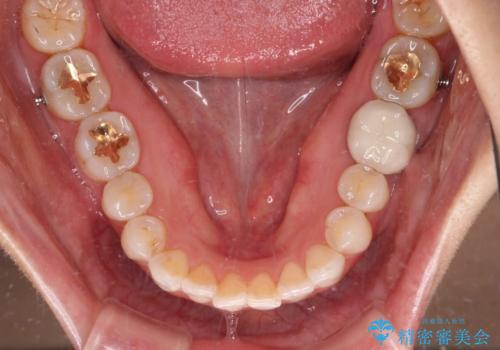

- 前歯のデコボコと上下スペースと前歯の隙間を気にして来院された患者様です。

目立たない装置を希望とのことでインビザラインにより、デコボコを解消しつつ、上下の前歯の隙間を閉じていくこととしました。

デコボコはあっという間に解消されましたが、上下前歯の隙間がなかなか解消されませんでした。

飲み込みの際に舌を前方に突出する癖があり、飲み込みの度に前歯に強く接触していたため、上下前歯の隙間が維持されていました。

舌の訓練を徹底していただいたことで、徐々に隙間は解消され、きれいな歯列に整えることができました。